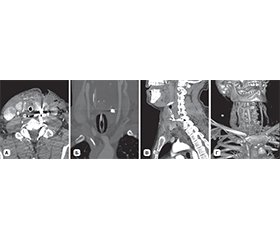

Актуальність. У статті проведений аналіз обстеження та лікування вогнепальних поранень шиї з ушкодженням щитоподібної залози (ЩЗ) за останні три роки в умовах Військово-медичного клінічного центру Північного регіону КМС ЗСУ. Мета: розробка та впровадження класифікації вогнепальних поранень шиї з ушкодженням ЩЗ. Матеріали та методи. Усі пацієнти були чоловічої статі, мали вогнепальні осколкові поранення шиї. Виконані лабораторні дослідження, ультразвукове дослідження шиї, мультиспіральна комп’ютерна томографія голови, шиї, органів грудної клітки та черевної порожнини, таза з контрастуванням та без, рентгенографічні дослідження органів грудної клітки та черевної порожнини, відеоезофагогастродуоденоскопія та відеобронхоскопія, електрокардіографія. Результати. Частота вогнепальних поранень шиї з ушкодженням ЩЗ за роками (2022, 2023, 2024) становить 5,2; 9,3; 8,7 %. Частота ушкоджень ЩЗ вогнепального походження за останні 2 роки збільшилась, що пов’язано із застосуванням противником дронів. У середньому, за нашими даними, ушкодження ЩЗ серед вогнепальних поранень шиї з ушкодженням порожнистих та паренхіматозних органів становить 7,5 %. Класифікація побудована на основі даних обсягу ушкодження, відповідної тактики лікування та можливої замісної гормональної терапії (якщо не було її призначено до поранення), які розподілені за класами. За обсягом ушкодження розподіл такий: І клас — забій ЩЗ, ІІ клас — поверхневе ушкодження (до 0,5 см глибиною), ІІІ клас — глибоке ушкодження, до 50 % частки, ІV клас — глибоке ушкодження, більше ніж 50 % частки, V клас — розтрощення ЩЗ. За класами частота ушкоджень ЩЗ розподілена: ІІ клас — 41,4 %, І клас — 34,3 %, ІІІ клас, клиноподібна або крайова резекція, резекція полюса або перешийка — 20,7 %, ІV клас, гемітиреоїдектомія — 3,4 %, V клас, тиреоїдектомія — 0 %. Усі поранення були осколковими. Ізольованих поранень ЩЗ не визначалось, що пов’язано з її анатомічним розташуванням. За тактикою лікування: ІІ клас, первинна хірургічна обробка рани — 41,4 %, І клас, консервативна терапія — 34,3 %, ІІІ клас — 20,7 %, ІV клас — 3,4 %, V клас — 0 %. Замісна гормональна терапія була в подальшому призначена пацієнтам з ІV класом. Середній термін лікування становив 10,2 ± 1,3 доби. Висновки. Вогнепальні поранення шиї з ушкодженням ЩЗ є рідкісною патологією. Запропонована класифікація дозволяє визначитися з лікувальною тактикою та прогнозом. Анатомічні та фізіологічні особливості ЩЗ повинні братися до уваги при оперативному лікуванні ЩЗ при її ушкодженні. Оперативні втручання з приводу ушкоджень ЩЗ слід проводити на рівні ROLE IV за наявності відповідних фахівців та обладнання.

Background. The article analyzes the examination and treatment of gunshot wounds of the neck with damage to the thyroid gland (TG) over the past 3 years in the conditions of the Military Medical Clinical Center of the Northern Region of the Medical Forces Command. The aim is to develop and implement a classification of gunshot wounds of the neck with damage to the TG. Materials and methods. All patients were male, had gunshot shrapnel wounds of the neck. Laboratory tests were performed, as well as ultrasound examination of the neck, multispiral computed tomography of the head, neck, chest and abdominal organs, pelvis with and without contrast, X-ray examinations of the chest and abdominal organs, video esophagogastroduodenoscopy and video bronchoscopy, electrocardiography. Results. The frequency of gunshot wounds to the neck with damage to the TG by years (2022, 2023, 2024) is 5.2, 9.3, 8.7 %. It has increased over the past 2 years, which is associated with the use of drones by the enemy. On average, according to our data, thyroid injuries among gunshot wounds to the neck with damage to hollow and parenchymal organs account for 7.5 %. The classification is based on the extent of the injury, appropriate treatment, and possible hormone replacement therapy (when it was not prescribed before the injury), which are distributed by class. The distribution by the extent of damage is as follows: сlass I — contusion of the TG, сlass II — superficial damage (up to 0.5 cm deep), сlass III — deep damage, up to 50 % of the lobe, сlass IV — deep damage, more than 50 % of the lobe, сlass V — crushing of the TG. The frequency of thyroid injuries is distributed by class: class II — 41.4 %, class I — 34.3 %, class III — wedge or marginal resection, pole or isthmus resection: 20.7 %, class IV — hemithyroidectomy: 3.4 %, class V — thyroidectomy: 0 %. All injuries were shrapnel. Isolated injuries of the TG were not identified, which is associated with its anatomical location. According to treatment, class II — primary surgical wound treatment: 41.4 %, class I — conservative therapy: 34.3 %, class III — 20.7 %, class IV — 3.4 %, class V — 0 %. Hormone replacement therapy was subsequently prescribed to patients with class IV. The average duration of treatment was 10.2 ± 1.3 days. Conclusions. Gunshot wounds of the neck with damage to the TG are a rare pathology. The proposed classification allows us to determine the treatment and prognosis. The anatomical and physiological features of the TG should be taken into account during surgical treatment for thyroid injury. Surgical interventions for thyroid injuries should be performed at the Role IV with the availability of appropriate specialists and equipment.